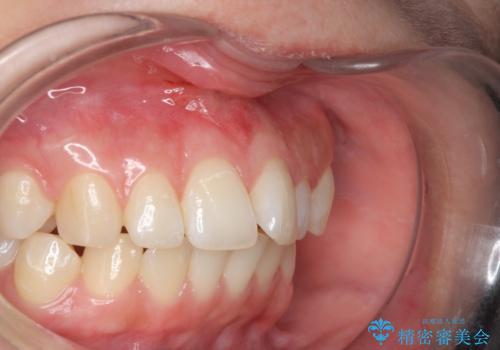

上唇小帯切除

- 上唇小帯切除術 3.3万円費用は治療当時の料金となります

矯正をする時、上唇小帯が残っているときれいに前歯が並ばない事があり、

矯正ができても上唇小帯のせいで前歯が後戻りする原因にもなります。